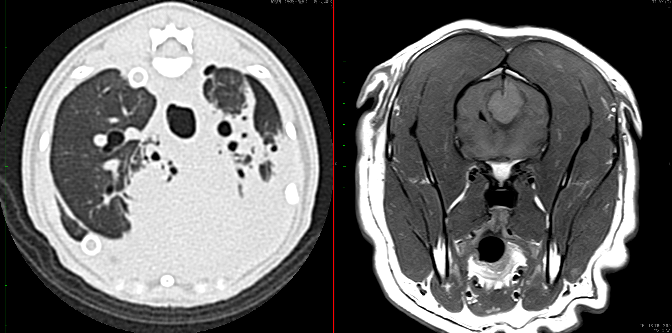

獣医療は医療技術の進歩により、愛玩動物の寿命が年々延びていることから、さらに複雑な疾患を対象にしなければならず、獣医師、動物看護師がチーム一丸となって適切な治療を行う必要性があります。

このため、動物医療センターには最新の放射線治療装置をはじめとする高度医療機器が設置され、学生実習をサポートできる専任の獣医師、動物看護師の指導の下、最先端の知識や技術を習得できるようになっています。